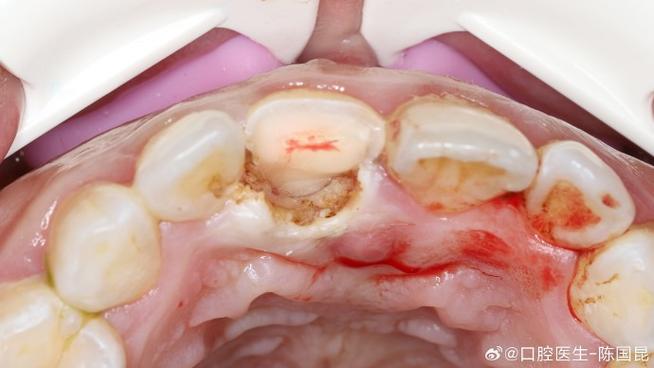

种植牙植骨手术中的创伤面主要指手术操作导致的骨组织、软组织(牙龈、黏膜)的缺损或损伤,根据发生部位和性质可分为以下几类:

这是植骨手术的核心创伤面,主要由患者自身骨量不足引起,长期缺牙后牙槽骨发生吸收、萎缩,或因外伤、肿瘤切除导致骨缺损,为容纳种植体,需通过植骨材料(如自体骨、异体骨、骨替代材料)重建骨组织,形成骨缺损区的“填充性创伤面”,种植窝预备过程中,若钻头转速、冷却不当,可能导致骨组织热损伤,形成“热灼伤创伤面”,影响骨细胞活性。

植骨材料(如骨粉、骨膜)植入后,与自身骨组织、软组织接触的界面存在“生物机械性创伤面”,材料颗粒间可能残留死腔,若与血液、组织液结合不充分,易形成纤维包裹,影响骨整合。